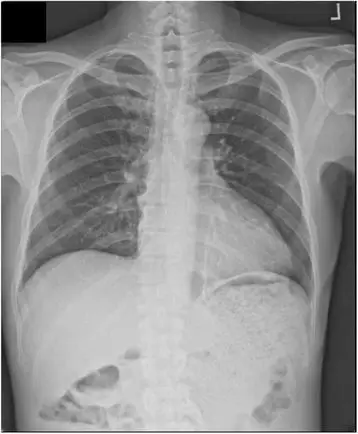

03胸部——先看DR,细看CT

DR可粗略检查肺、心影、主动脉弓、肋骨等,可以检查有无肺纹理增多、肺内较大肿块、主动脉结钙化等。胸部CT检查显示出的结构更清晰,对胸部病变检出敏感性和准确性均优于常规X光胸片,特别是对于筛查早期肺癌有重大意义。